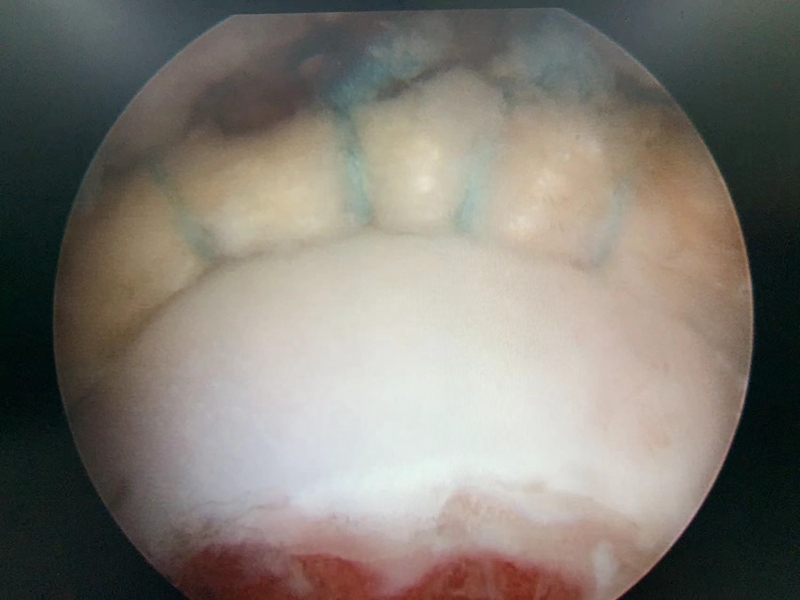

图4 髋关节镜术中图片,可见明显盂唇撕裂伴充血

图10 髋关节盂唇损伤及修复